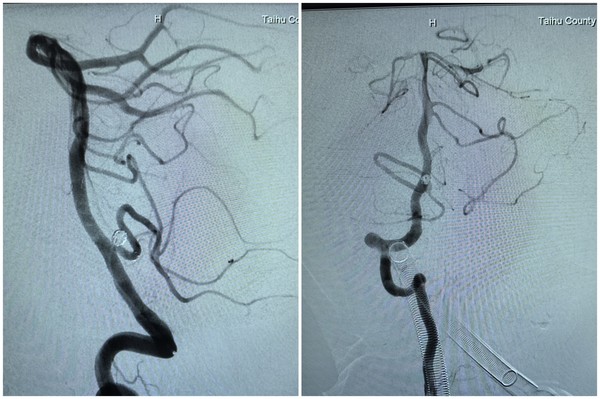

手术当天,在 DSA 设备实时引导下,介入医生先为患者进行右侧股动脉、右侧桡动脉穿刺置管,成功建立双通道。随后,通过股动脉通路,利用翻山技术将支架微导管置入右侧小脑后下动脉;同时通过桡动脉通路,将弹簧圈微导管精准送入动脉瘤腔内。团队先填入几枚不同规格的弹簧圈,再沿支架微导管释放一枚颅内支架,实现对动脉瘤的完全覆盖。术中造影显示,动脉瘤已完全隔绝,基底动脉、右侧小脑后下动脉血流通畅,未出现血管狭窄或栓塞迹象,整个手术历时 2 小时顺利完成。​

WPS拼图术后1.jpg

术后 6 小时,患者意识清醒,四肢活动正常,经神经功能评估未出现任何并发症;术后复查头颅磁共振,也未发现急性脑梗死。“不用开颅,睡一觉手术就做完了,县医院的技术真是高超!” 患者对此次微创介入治疗的效果赞不绝口。​